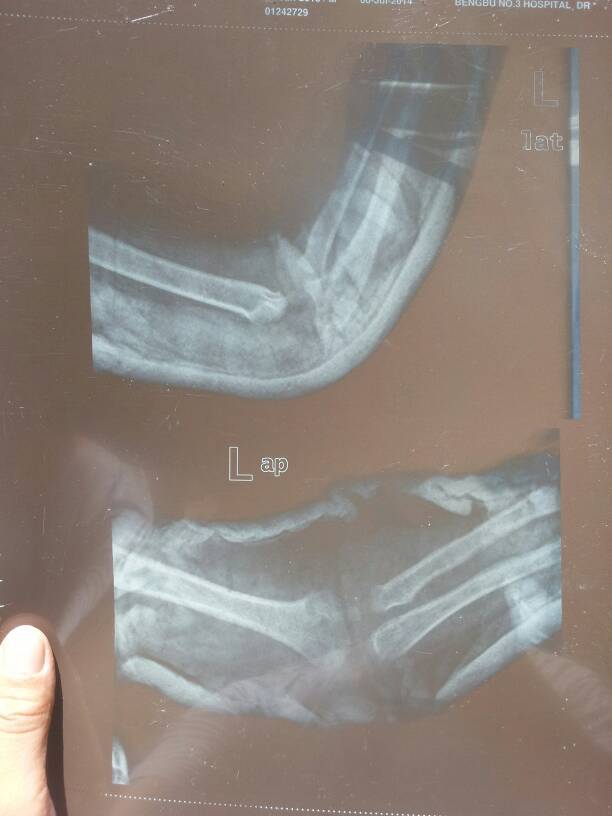

小孩1周11个月左胳膊肘摔着了,医生帮我看下有没有问题 点击展开 匿名用户 2014-07-22 11:13 为您推荐: 其他回答 你好,现在这个时候也不要太担心这个情况的话自己还是要注意在医院里,给宝宝,好好的做一下康复的, 生活还在继续66 2014-07-23 05:50 相关问题 怀孕29周两天,今天去做B超医生说宝宝头大,小孩大了点,怎么回事啊? 孕十四周去医院做彩超,医生总说小孩趴着,测不到脖子和鼻梁,该怎么办? 我怀孕3个月11天去检查医生说小孩头不圆疙瘩不平,还说孩子有点小这是怎么回事?